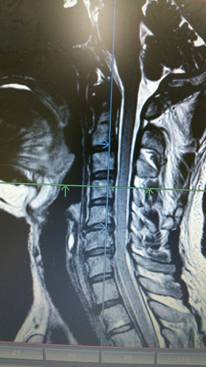

頚椎ヘルニアを専門に治療する整骨院です。交通事故むち打ち治療

手術を考慮された患者さんです。

そもそも医者と患者では、手術に対する意識に大きなギャップがある。その「埋められない溝」について

「患者さんは手術成功と聞くと、『今ある苦しみから解放される』と期待します。一方で、医者としては『このまま放っておくと、亡くなってしまうが、手術することによって寿命が延びる可能性が高まる』という視点。患者側は劇的な改善を求めるのに対し、医者側は命を助けることを最優先にしている。

医学論文の一般的な定義でいうと、『オペ後30日以内』に死亡したかどうかが指標になる。つまり30日生きていれば、患者の回復レベルがどうであれ、手術は『成功』としてカウントされるのです」